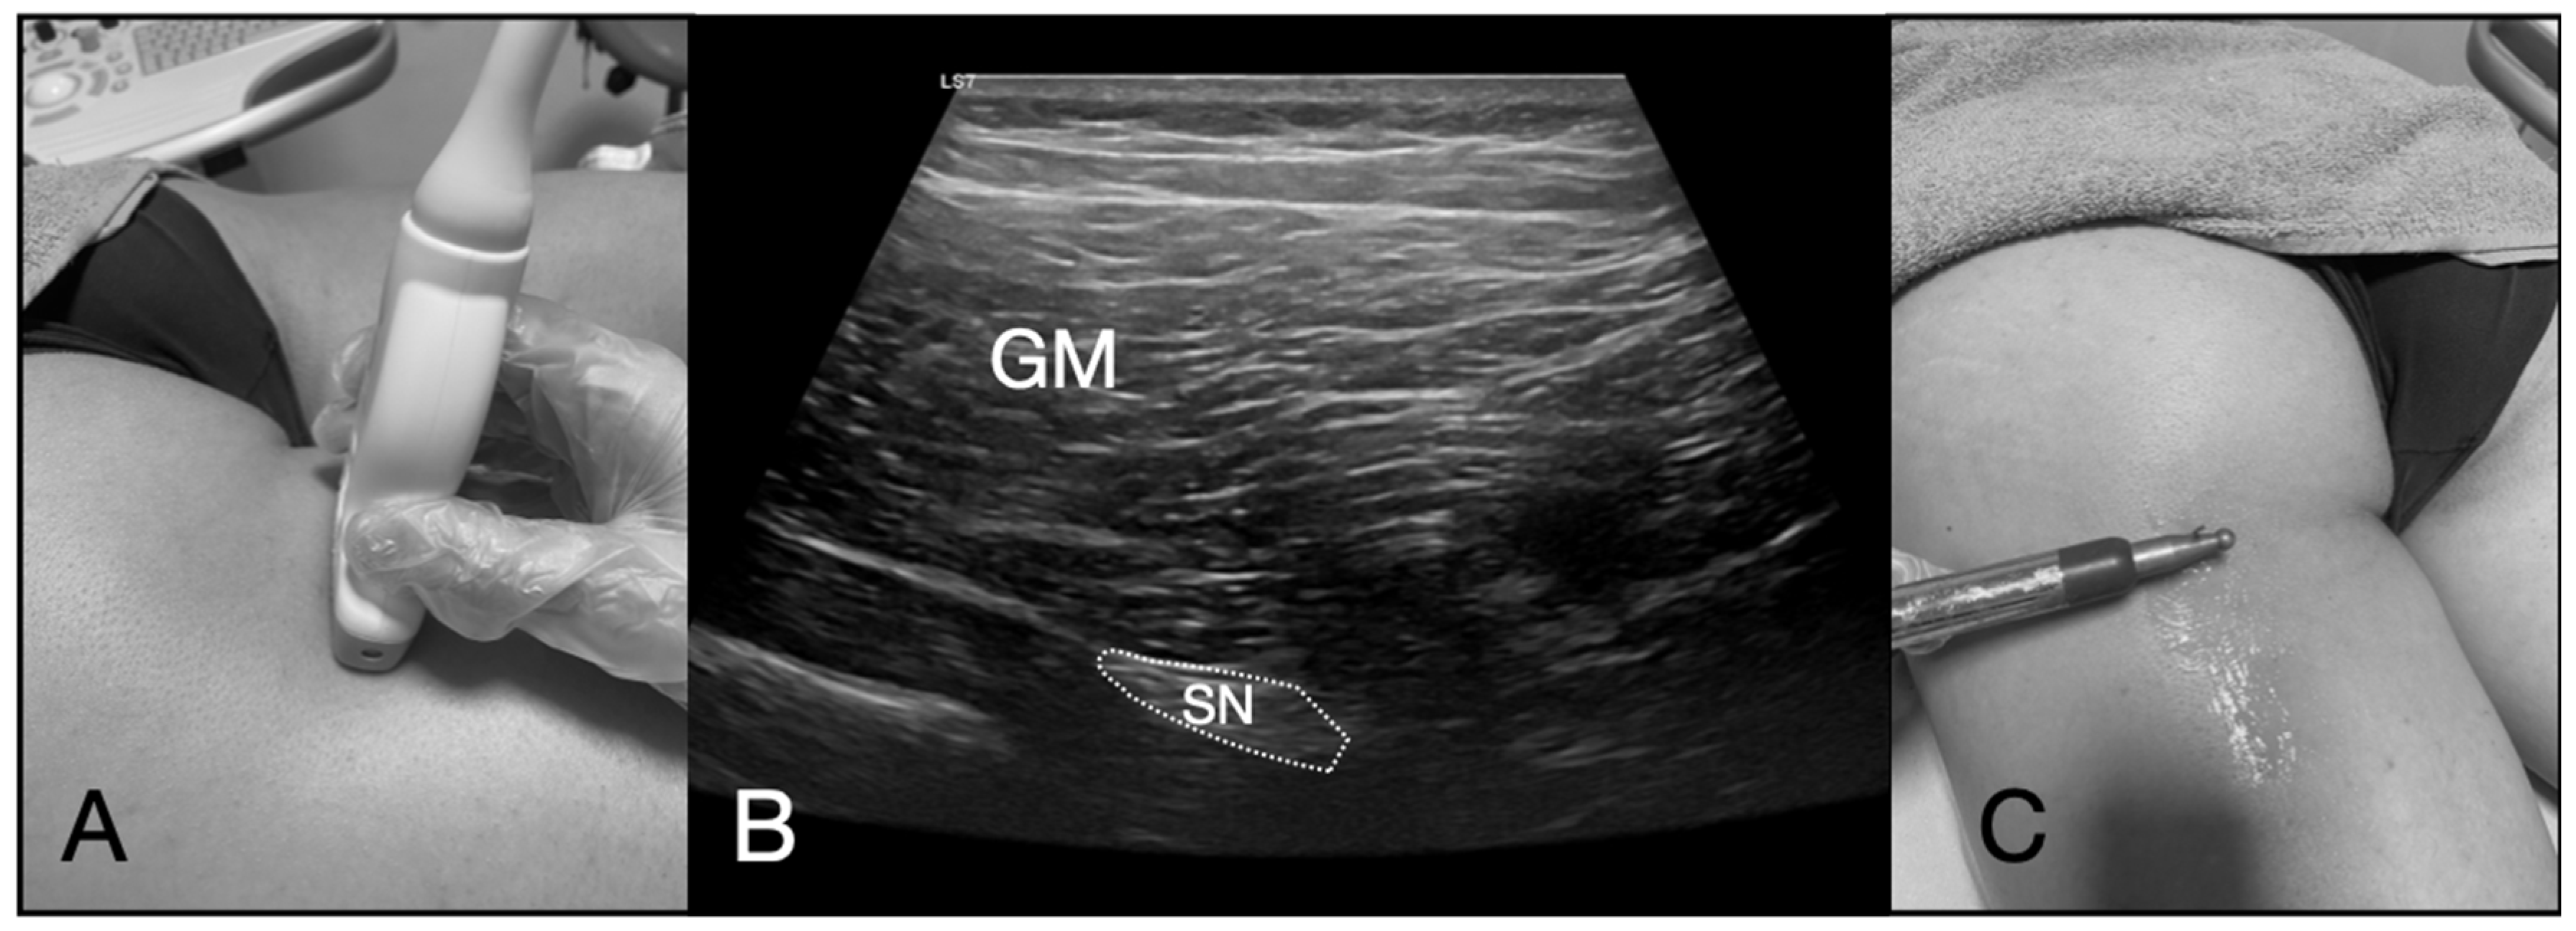

2.5. Ultrasound-Guided PNM Intervention